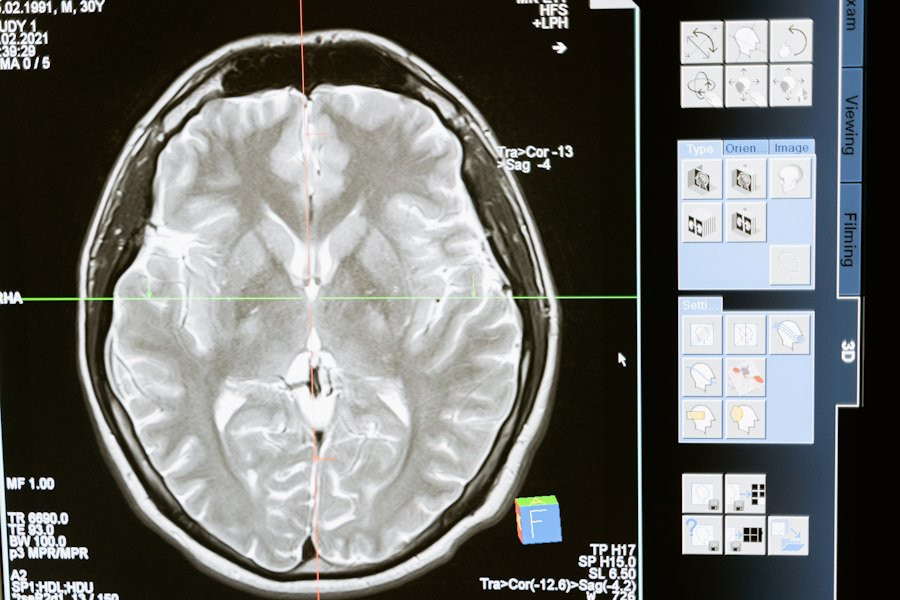

Фото из открытых источников

Изыскания, проведенные учеными LMU Munich (Германия), раскрыли ключевые механизмы регенерации нервных клеток мозга, что может пролить свет на новые методы лечения неврологических заболеваний. Исследование, опубликованное на портале Nature Neuroscience, сосредоточилось на прямом нейрональном перепрограммировании, процессе, позволяющем преобразовывать локальные глиальные клетки в функциональные нейроны.